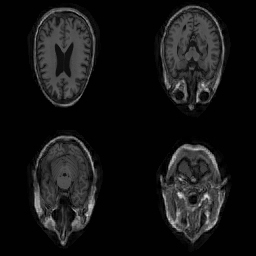

| Original | Renderings after de-identification | Original | MRI slices after de-identification | ||||||

| CP-GAN | FACE MASK | DEFACE | QUICKSHEAR | CP-GAN | FACE MASK | DEFACE | QUICKSHEAR | ||

Benchmark De-Identification Methods. We compare our result with three publicly available and widely-established methods for de-identification of MRI head scans, depicted in Figure 3. All methods have in common that they (1) are not deep-learning-driven, (2) require no additional training and (3), are used on a day-to-day basis in neuroscience and clinical research. All procedures were applied with default settings on images of resolution . The methods include QUICKSHEAR [Schimke et al.(2011)Schimke, Kuehler, and Hale], FACE MASK [Milchenko and Marcus(2013)], and DEFACE [Bischoff-Grethe et al.(2007)Bischoff-Grethe, Ozyurt, Busa, Quinn, Fennema-Notestine, Clark, Morris, Bondi, Jernigan, Dale, Brown, and Fischl]. Descriptions of the methods are provided in the Appendix. We also include MRI WATERSHED [Ségonne et al.(2004)Ségonne, Dale, Busa, Glessner, Salat, Hahn, and Fischl], a skull-stripping method that removes everything except the brain.